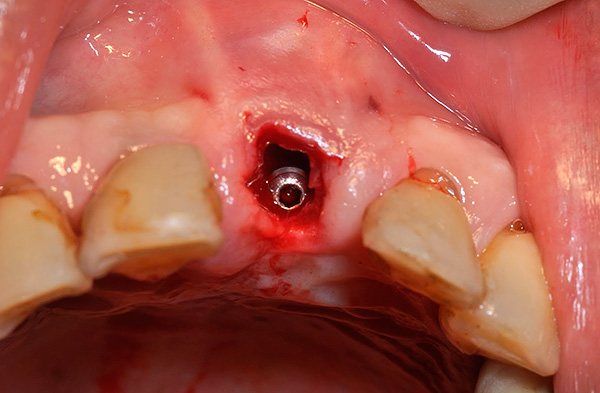

На фотографиях ниже показаны удаленные импланты:

После удаления подвижного импланта проводят процедуру комплексной подготовки лунки к следующей имплантации, которую могут осуществить уже через 1-2 месяца. Например, при значительной убыли костной ткани или близости к гайморовой пазухе может потребоваться наращивание кости челюсти под зубной имплант (операция синус-лифтинга).